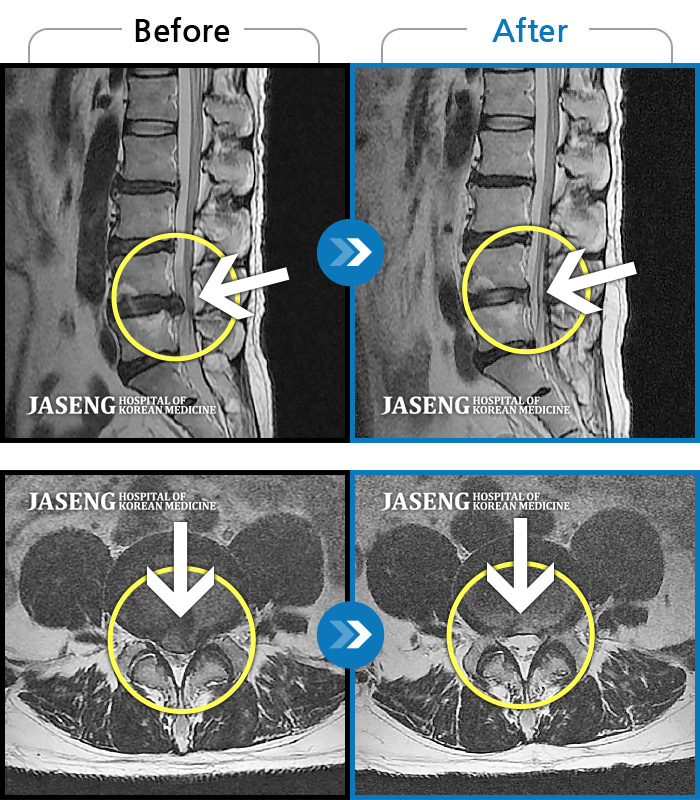

MRI 치료사례

허리디스크

일산 · 김진수 원장

우측 골반 통증이 심하고 우측 하지로 당김과 저림이 지속되었습니다. 야간통이 심하여 야간 수면 제한이 되는 등 중등도 이상의 통증을 호소하는 상태였습니다.

촬영시기

2021.03.22 ~ 2025.09.30

2025.10.30